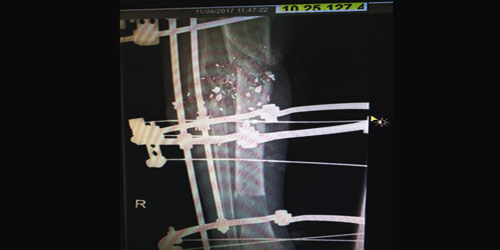

تمكن فريق طبي متخصص في جراحة العظام بمستشفى الملك فهد المركزي بجازان من إجراء عملية نوعية للتعويض عن عظم مفقود من ساق شاب سعودي تعرض لحادث أدى إلى تفتت في عظم الساق مع فقد عظم بطول 7سم.وقد تمت العملية على مرحلتين الأولى تنظيف الجروح وتركيب جهاز (أليزاروف) وعمل قص عظمي وتطويل تدريجي لتعويض العظم من نفس الساق، وتضمنت المرحلة الثانية طعم عظمي عند التقاء أطراف العظمتين وقد تمت العملية بنجاح بحمد الله.